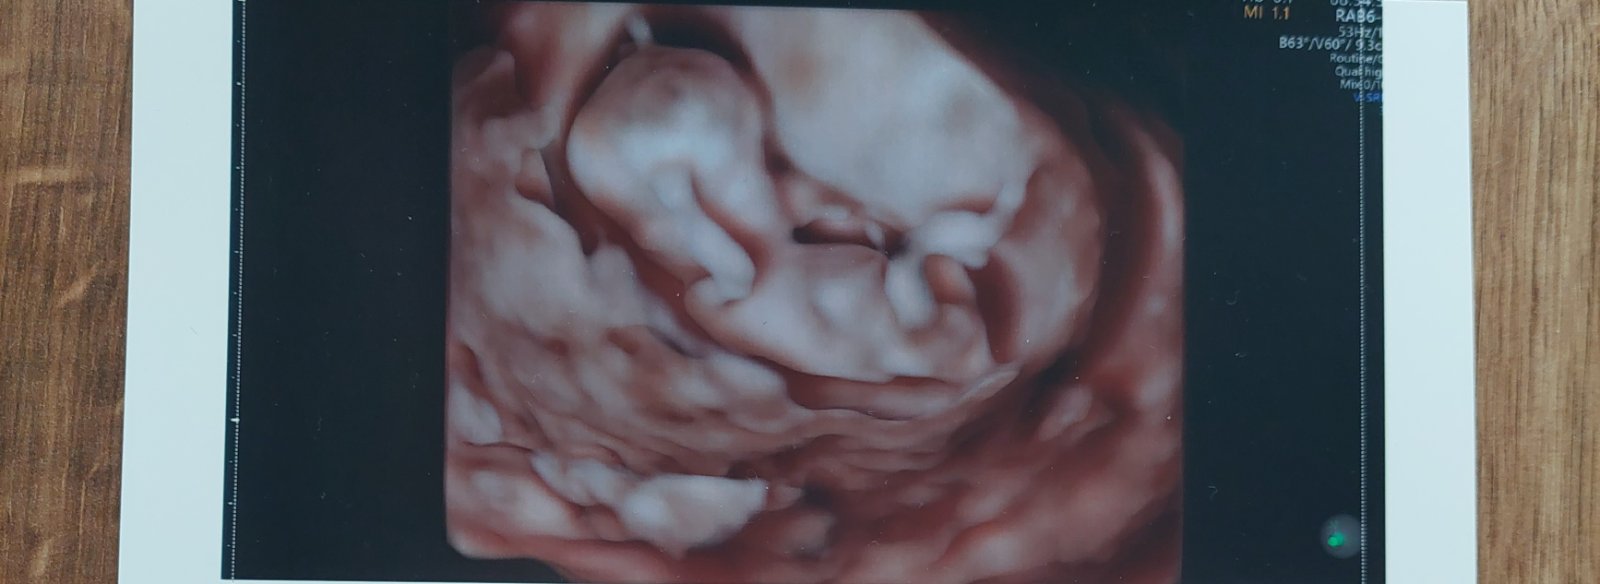

Ako zistiť pohlavie v 12. týždni tehotenstva?

ahoj, podla mna sa to este moc neda rozoznat ja som bola dnes na sone 14tt a nevedela mi povedat ani cez 3D sono